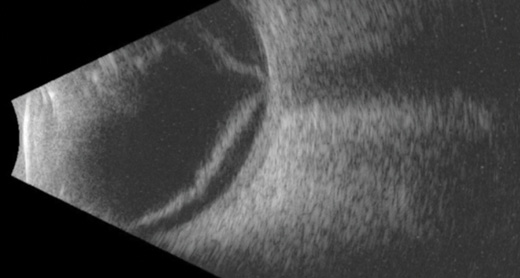

Figure 1. Horizontal B-scan ultrasound confirming macula-off retinal detachment.

An 82-year-old man with a history of Stephens-Johnson disease and an aphakic type 1 Boston KPro underwent pars plana vitrectomy and vitreous chamber insertion of a Baerveldt 250 glaucoma drainage implant (Abbott Laboratories, Inc.). As a result of inferior and nasal retinal detachment, his visual acuity had declined from 20/200 to finger counting. B-scan ultrasound confirmed that the macula was detached (Figure 1). A retroprosthetic membrane was also noted.